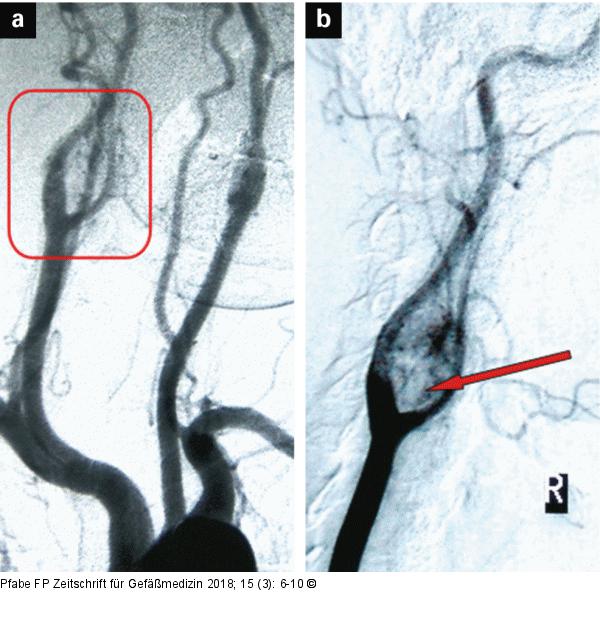

Abbildung 4a-b: Digitale Subtraktionsangiographie Digitale Subtraktionsangiographie. (a): Übersichtsaufname (RAO 30°) mit Darstellung der Auftreibung der rechten Karotisbifurkation; (b): selektive Darstellung der Karotiden rechts (LAO 30°) mit Visualisierung der Hypervaskularisation des Glomus caroticum-Tumors (roter Pfeil). |